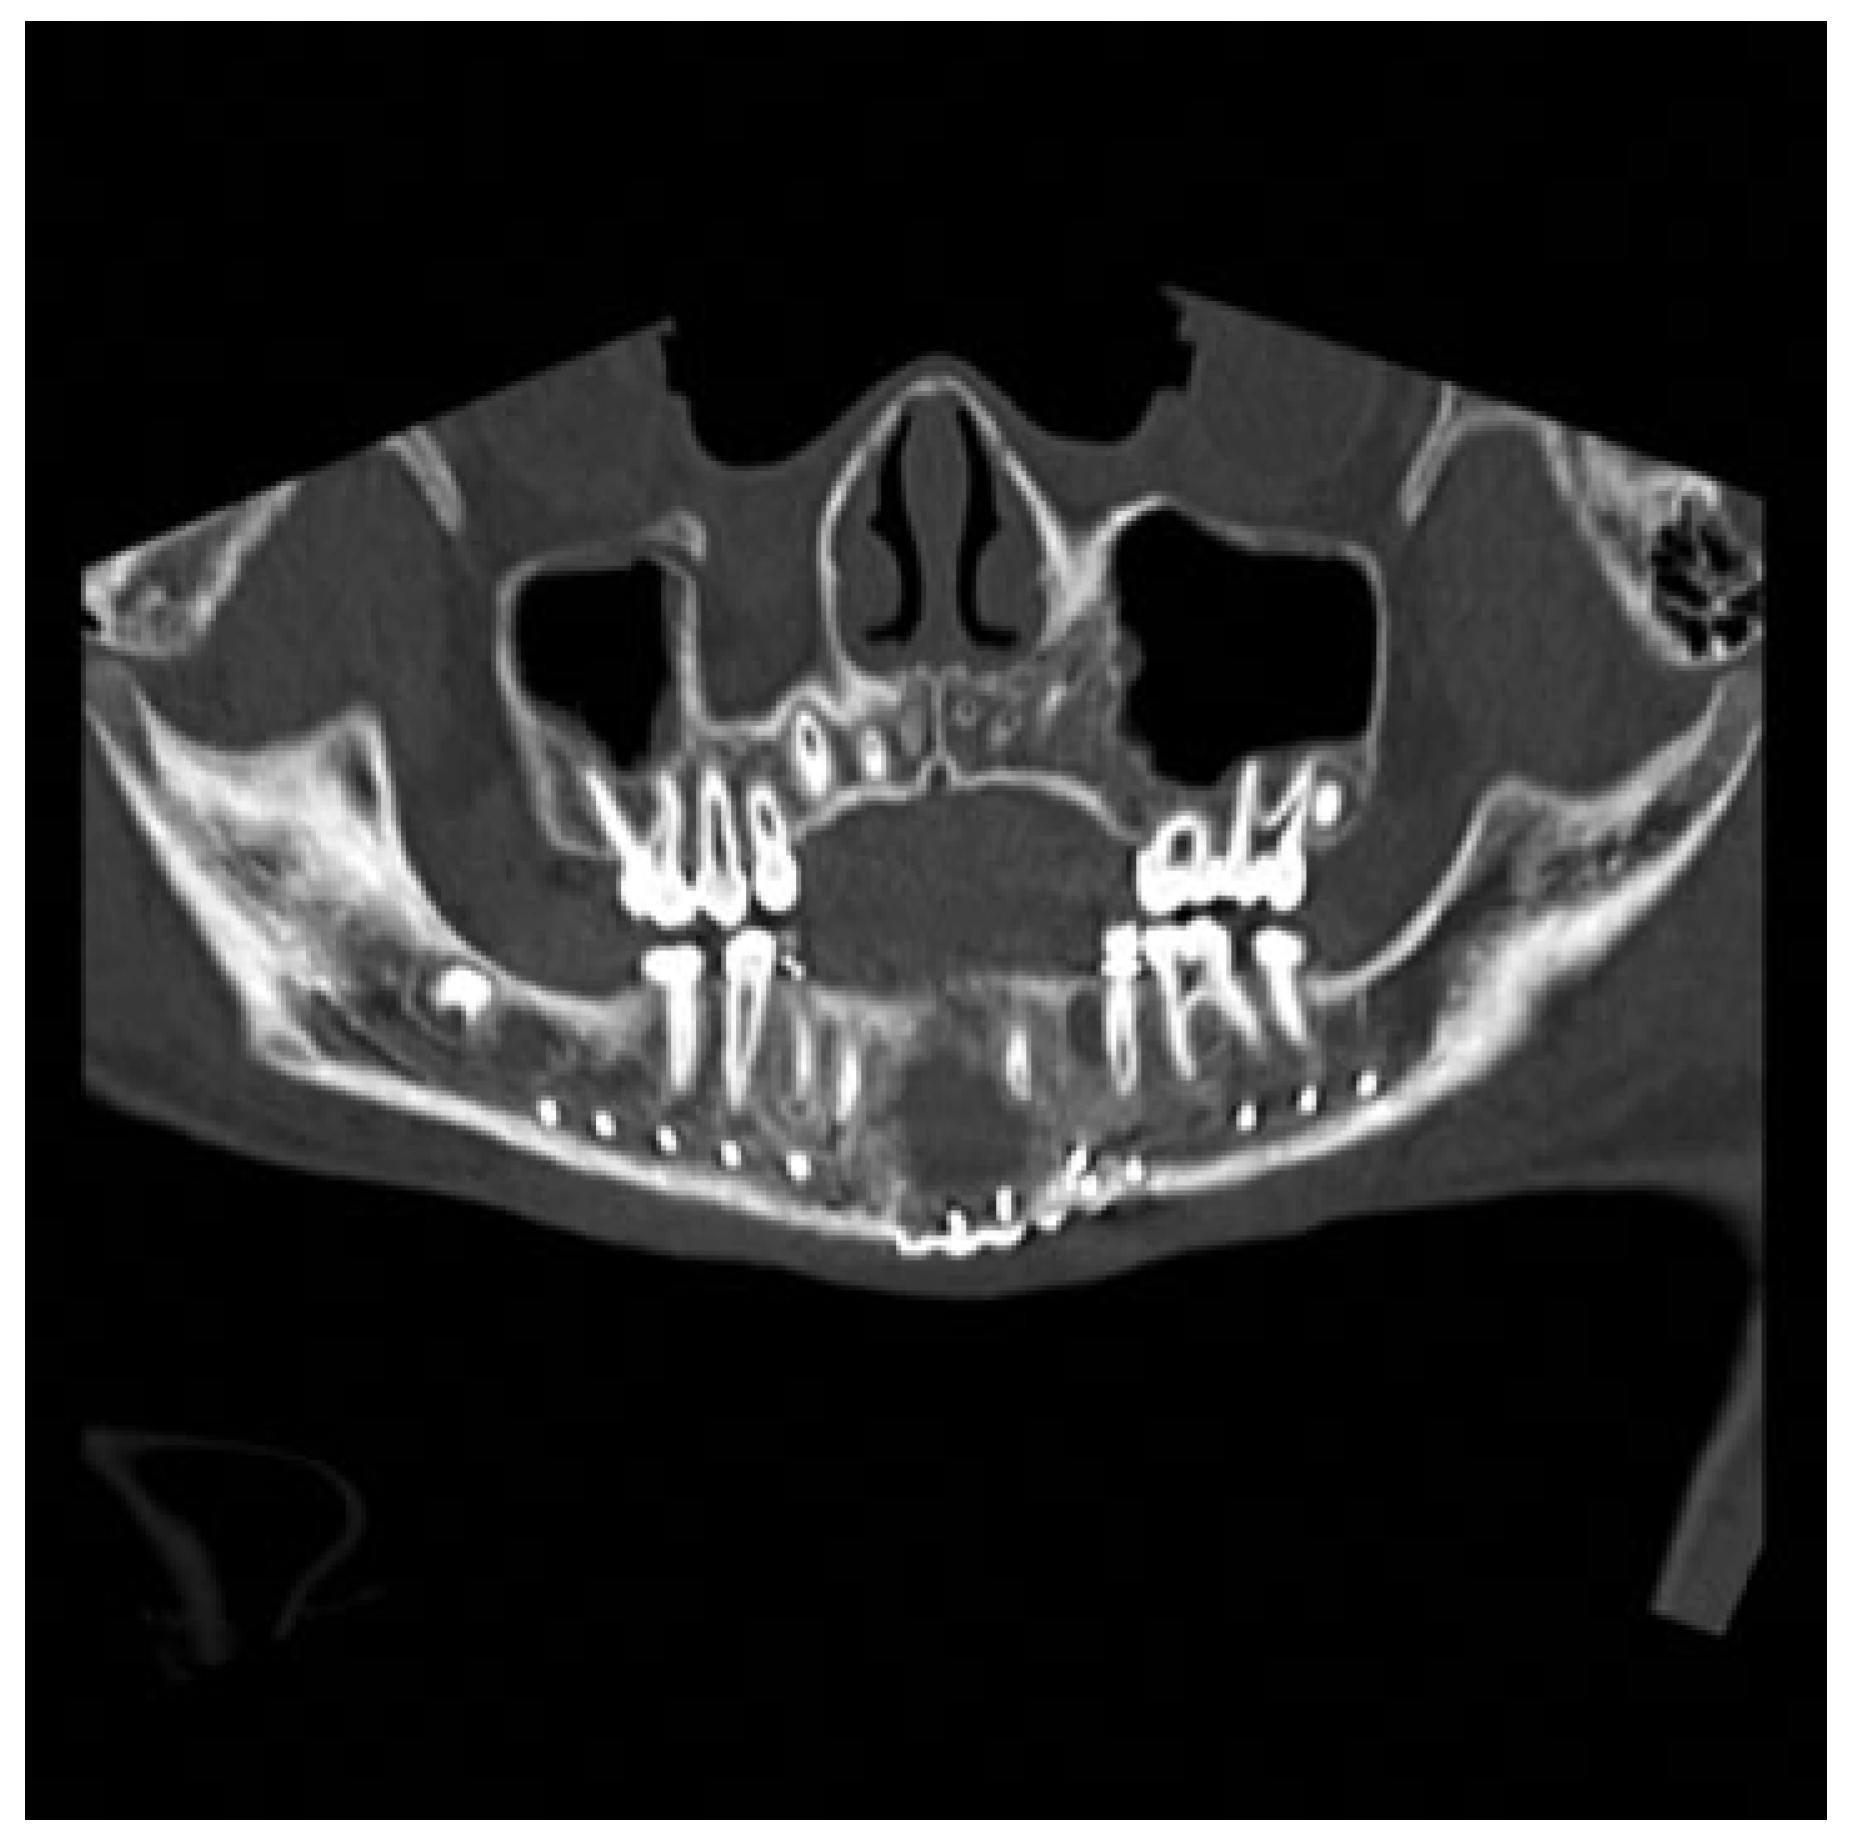

Figure 4.

Panorex computed tomography scan obtained in the immediate postoperative period showing improved anatomic alignment.